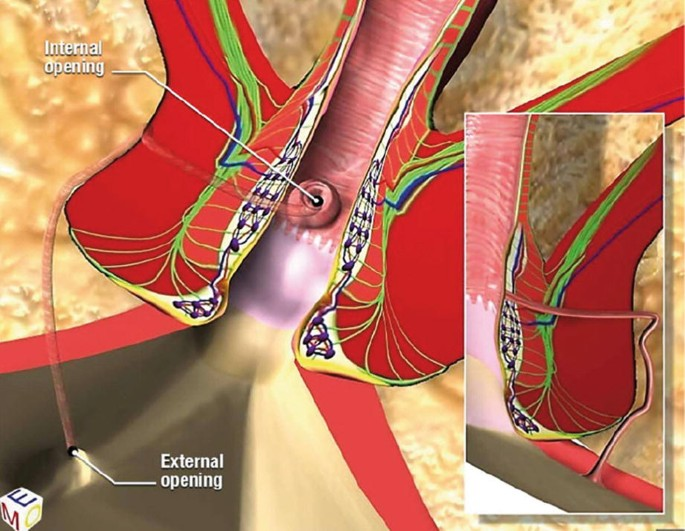

VAAFT (Video-Assisted Anal Fistula Treatment) is a modern, minimally invasive technique used to treat anal fistulas ...

What is VAAFT and How Does It Treat Fistula-in-Ano?

Many patients come to us with a common question: “Doctor, can Anal Fistula …”